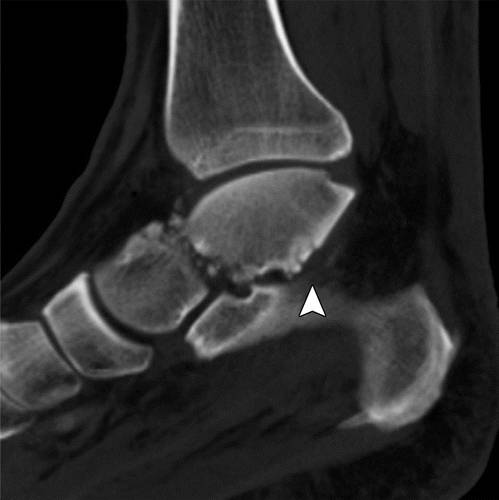

图10a粉碎性骨折冠状剪切距骨体断裂。 (a)该踝的外侧片显示距骨体(箭头)与在后距下关节突骨折碎片的冠剪切断裂。 (b)踝关节的AP射线照片显示后面小面(箭头)的揭示,与后股间关节的半脱位一致。 (c)矢状的CT图像显示了主要在冠状面中的距骨体的粉碎性骨折(箭头)。 在后距下关节处的骨折碎片存在前后牵引,导致半脱位(箭头)。

距骨体的剪切断裂通常由在高度跌倒或机动车辆事故的设置中的背屈脚上的轴向负载引起。 粉碎粉碎的距骨体外骨折对所有距骨损伤的预后最差(24)。 它们通常由于高能量冲击并且经常是开放性骨折。 骨丢失和非解剖复位的发生率高,并且随后出现缺血坏死。

初步诊断可以用放射线摄影,然后进行冠状和矢状重建到踝臼的CT,以评估粉碎,关节内累及手术计划(1,25,26)。